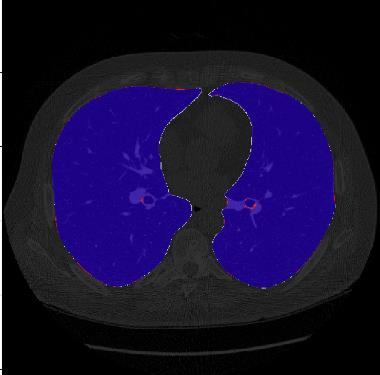

Segmentation of lung tissue in computed tomography (CT) images is a precursor to most pulmonary image analysis applications. Semantic segmentation methods using deep learning have exhibited top-tier performance in recent years. This paper presents a fully automatic method for identifying the lungs in three-dimensional (3D) pulmonary CT images, which we call it Lung-Net. We conjectured that a significant deeper network with inceptionV3 units can achieve a better feature representation of lung CT images without increasing the model complexity in terms of the number of trainable parameters. The method has three main advantages. First, a U-Net architecture with InceptionV3 blocks is developed to resolve the problem of performance degradation and parameter overload. Then, using information from consecutive slices, a new data structure is created to increase generalization potential, allowing more discriminating features to be extracted by making data representation as efficient as possible. Finally, the robustness of the proposed segmentation framework was quantitatively assessed using one public database to train and test the model (LUNA16) and two public databases (ISBI VESSEL12 challenge and CRPF dataset) only for testing the model; each database consists of 700, 23, and 40 CT images, respectively, that were acquired with a different scanner and protocol. Based on the experimental results, the proposed method achieved competitive results over the existing techniques with Dice coefficient of 99.7, 99.1, and 98.8 for LUNA16, VESSEL12, and CRPF datasets, respectively. For segmenting lung tissue in CT images, the proposed model is efficient in terms of time and parameters and outperforms other state-of-the-art methods. Additionally, this model is publicly accessible via a graphical user interface.